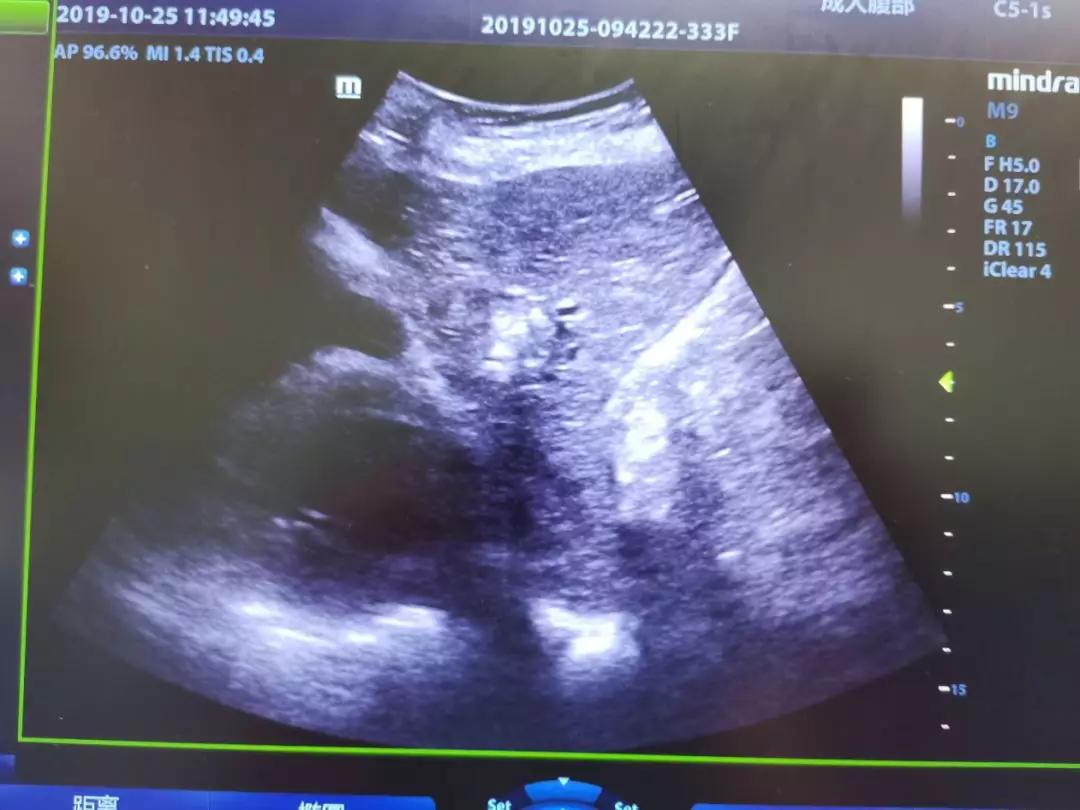

邻近心包的肝癌病灶

2019年9月,陕西中医药大学附属医院超声诊断科王涛医师在中国人民解放军总院(*013院医**)完成了为期6个月的进修学习,以优异成绩学成归来。经过一段时间的充分准备,在超声诊断科、介入组团队、肝病科、手术麻醉科等多学科的协助下,于2019年11月1日为一患者行超声引导下介入治疗。由于患者肿瘤位于S2段,一边紧邻胃肠,一边靠近心包,术前经超声诊断科主任姚秀芬,副主任骆会婷、肖迎聪以及肝病一科主任李京涛联合会诊,制定了详尽的介入消融术方案及应急措施。术中用人工腹水法隔离和保护周围脏器,精准进入瘤体进行射频治疗,消融形成的强回声区域逐渐覆盖瘤体,直至达到安全边界。随后即刻行超声声学造影,证实肿瘤及其周边组织完全灭活。手术共用时35分钟,过程顺利,患者无不良反应,安返病房。术后4小时患者排气,12小时人工腹水吸收完全。

超声造影是介入超声的一个好帮手,在整个手术的术前、术中、术后都需要用到超声造影。术前,主要是用来做评估是否需要做射频消融术及其范围。术中,超声造影可以引导射频消融术的位置。术后,主要是用于评估射频消融术的效果。多种超声技术的联合应用,可为肝癌精准的术前诊断、术中定位、术后评估起到重要作用。